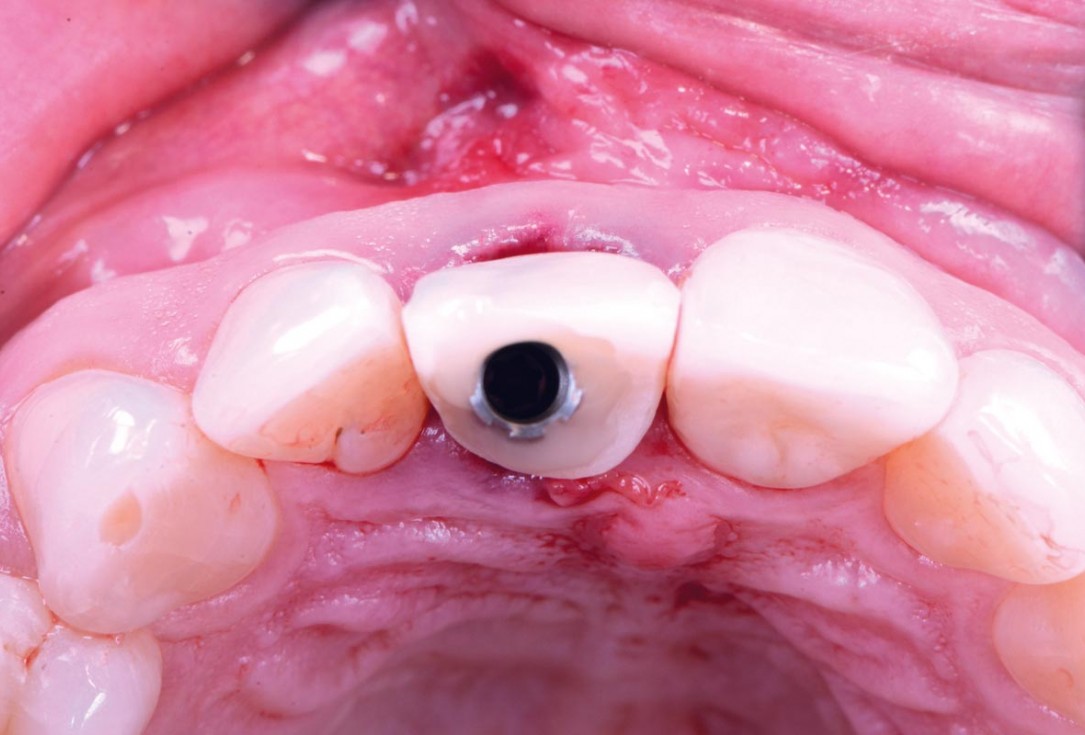

12/30 - Plastic temporary crown and 2.5 mm temporary abutmentExcellent aesthetic result of buccal augmentation with mucoderm® and maxgraft® after immediate implant placement - 3-years follow-up - Dr. A. Puišys